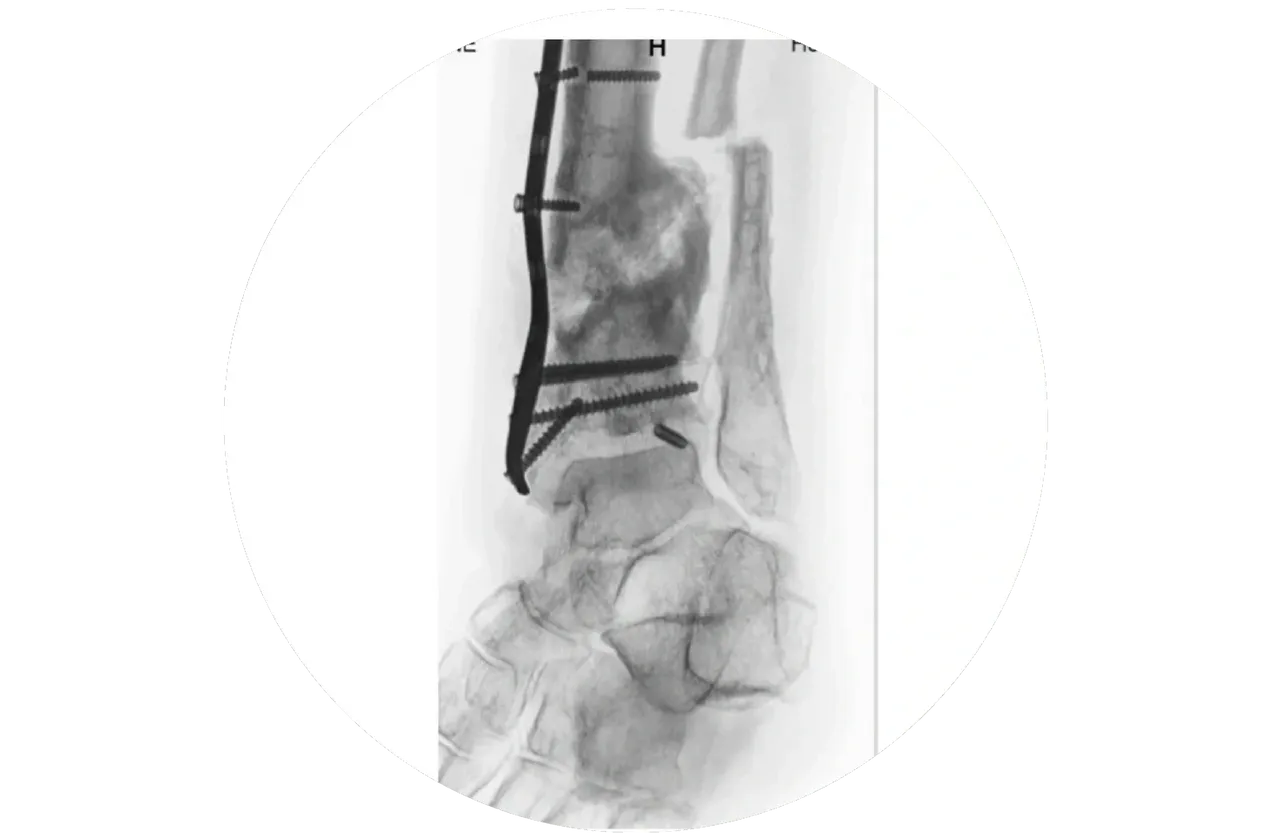

News 15 April, 2026NewsAscend Recovery in the heart of StellenboschDiscover more 5 December, 2025Limb LengtheningMetatarsal Lengthening for BrachymetatarsiaDiscover more 3 October, 2025Foot and Ankle SurgeryTransverse Bone TransportDiscover more 22 September, 2025Limb LengtheningFitbone Nail Limb LengtheningDiscover more 15 September, 2025Osseo-IntegrationOsseointegration Limb Replacement | Bone Anchored ProsthesisDiscover more 22 May, 2023Education360 LIMB RECONSTRUCTIONDiscover more 3 May, 2023GeneralLimb ReconstructionDiscover more 15 March, 2023Limb ReconstructionClosed distraction treatment of a long-standing tibial non-union.Discover more 15 March, 2023Limb ReconstructionNonUnion Tibia Treated by Closed Distraction with Ilizarov DeviceDiscover more 15 March, 2023Limb ReconstructionNon-Union Treatment By Internal FixationDiscover more 5 March, 2023Limb LengtheningNon-UnionsDiscover more 5 March, 2023News3D Printing in Limb Reconstruction SurgeryDiscover more